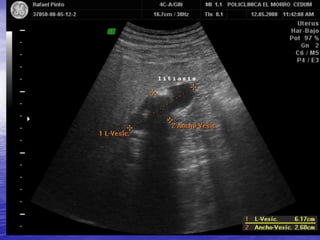

LITIASIS VESICULAR

ENGROSAMIENTO DIFUSO DE

LA PARED VESICULAR